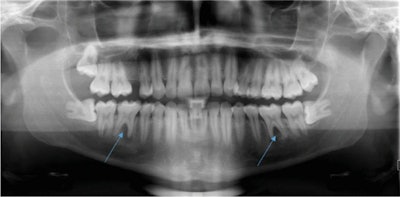

A healthy 28-year-old man with apical periodontitis on tooth #36 and #46 was referred by his primary dentist to the dental clinic at Saarland University. Though endodontic treatment had already begun, apical osteolysis was increasing on both teeth, according to the case report.

Upon examining the teeth, the dentist observed increased tooth mobility and bifurcation at a probing depth of 4 mm. The periodontal screening index was unremarkable, showing no signs of periodontal disease. However, tooth #36 and #46 each showed a 10-mm pocket with bleeding on probing at the vestibular central, and there was some bulging elastic swelling at the vestibulum, they wrote.

A percussion test was negative, and the exam and imaging revealed no anomalies, pulp calcifications, or formation defects of the hard tooth tissue. Also, there was no external resorption, root canal, or pulp chamber perforation, according to the report.

During a follow-up visit two weeks later, the patient reported having no pain. Also, the 10-mm pockets on the two teeth showed no bleeding on probing, and there was no mobility on tooth #46 and minimal mobility on tooth #36.

The clinicians went ahead and completed the root canals on the patient, the authors wrote. Since treatment has been completed, the patient has remained asymptomatic and regularly uses a bite split. One year after the root filling, he will undergo another x-ray.